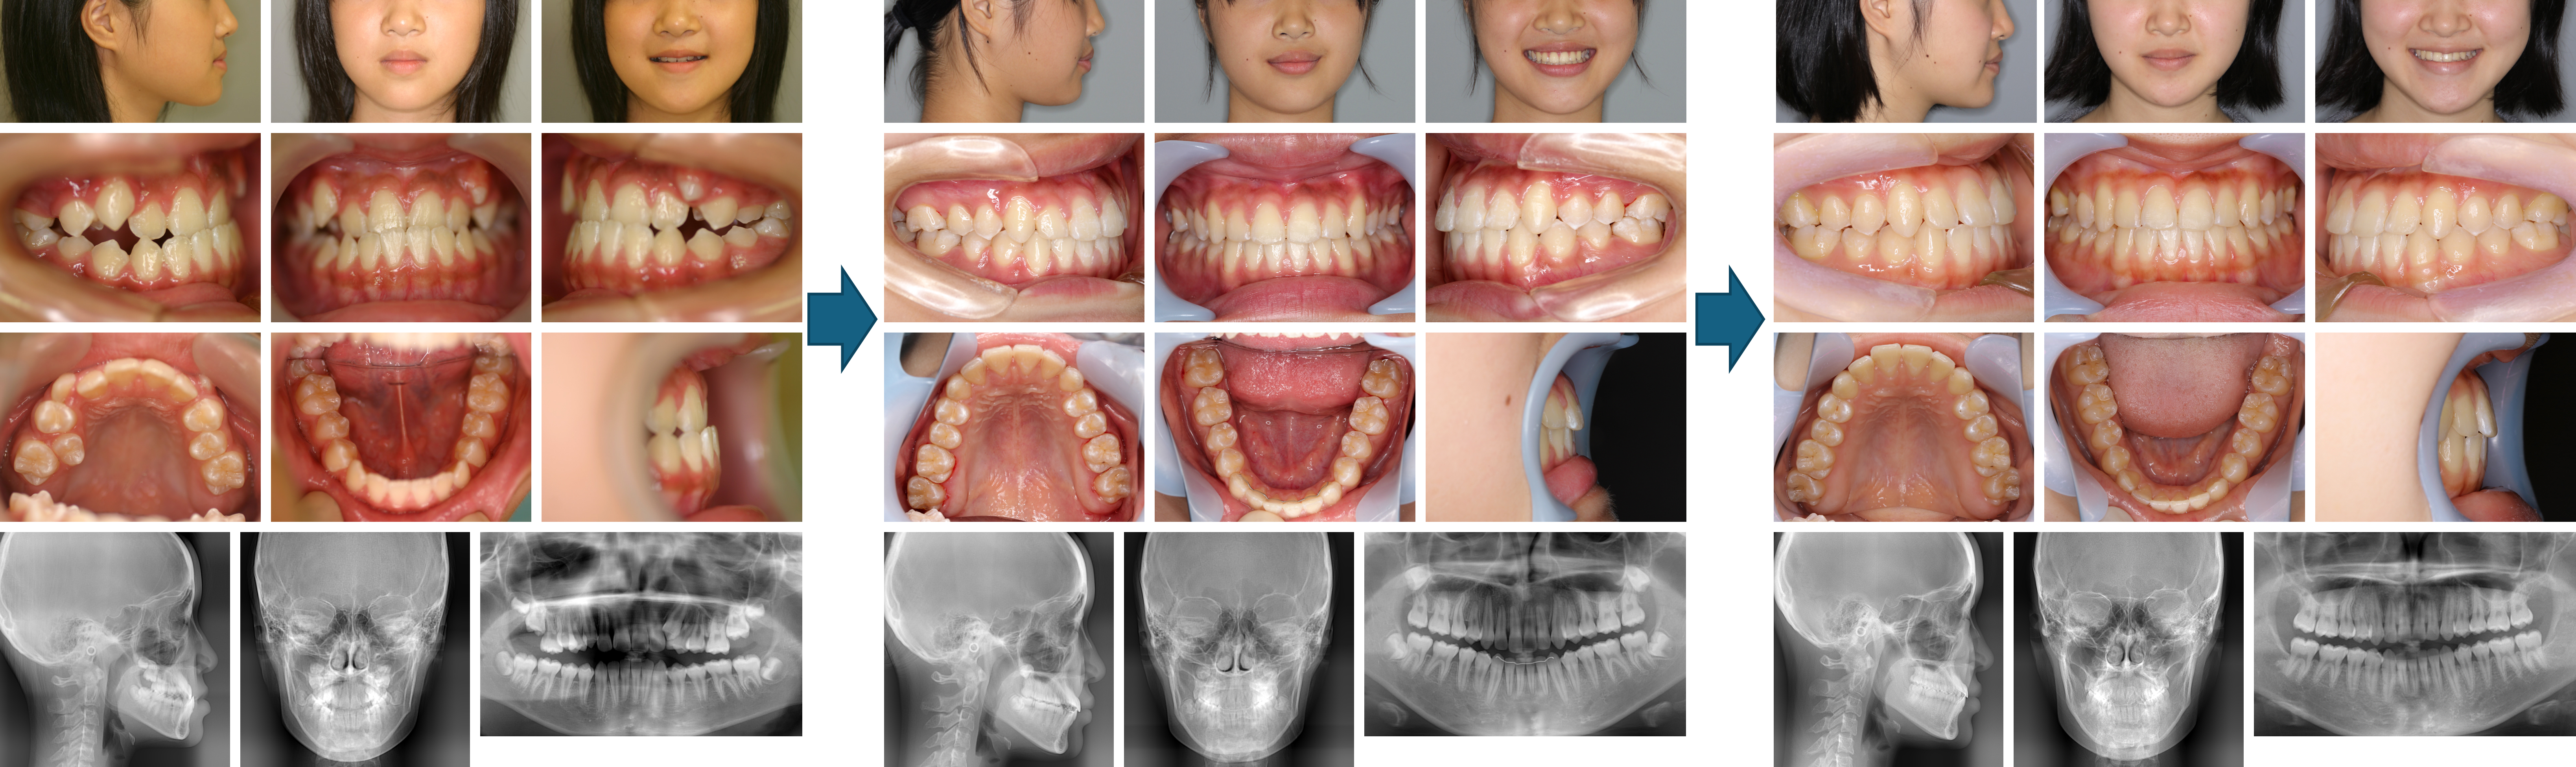

【治療例 K7047】初診時年齢:15歳7か月 / 性別:女性 / 主訴:下の歯並びがガタガタで磨きにくい

症例の概要:本症例は、下顎がやや前方に位置するⅢ級傾向の症例で、犬歯部に反対咬合がみられました。また、右側奥歯のかみ合わせが不安定な状態でした。右上5番、左上4番、左右下4番および親知らずを抜歯し、マルチブラケット装置による矯正治療を行いました。咬み合わせの安定と、よりバランスの取れた横顔を目標に治療を進めました。治療の結果、奥歯のかみ合わせはⅠ級となり、1歯対2歯の理想的な咬合関係を得ることができました。保定期間終了後も安定した状態を維持しております。

主訴:下の歯並びがガタガタで磨きにくい

診断名:上顎前歯の唇側傾斜を伴う骨格性Ⅲ級 Angle Class Ⅲ 叢生症例

使用した主な装置:マルチブラケット装置、顎間ゴム

抜歯/非抜歯および抜歯部位:抜歯(上顎左側第一小臼歯、上顎右側第二小臼歯、下顎両側第一小臼歯)

治療期間:3年2か月

治療回数:41回